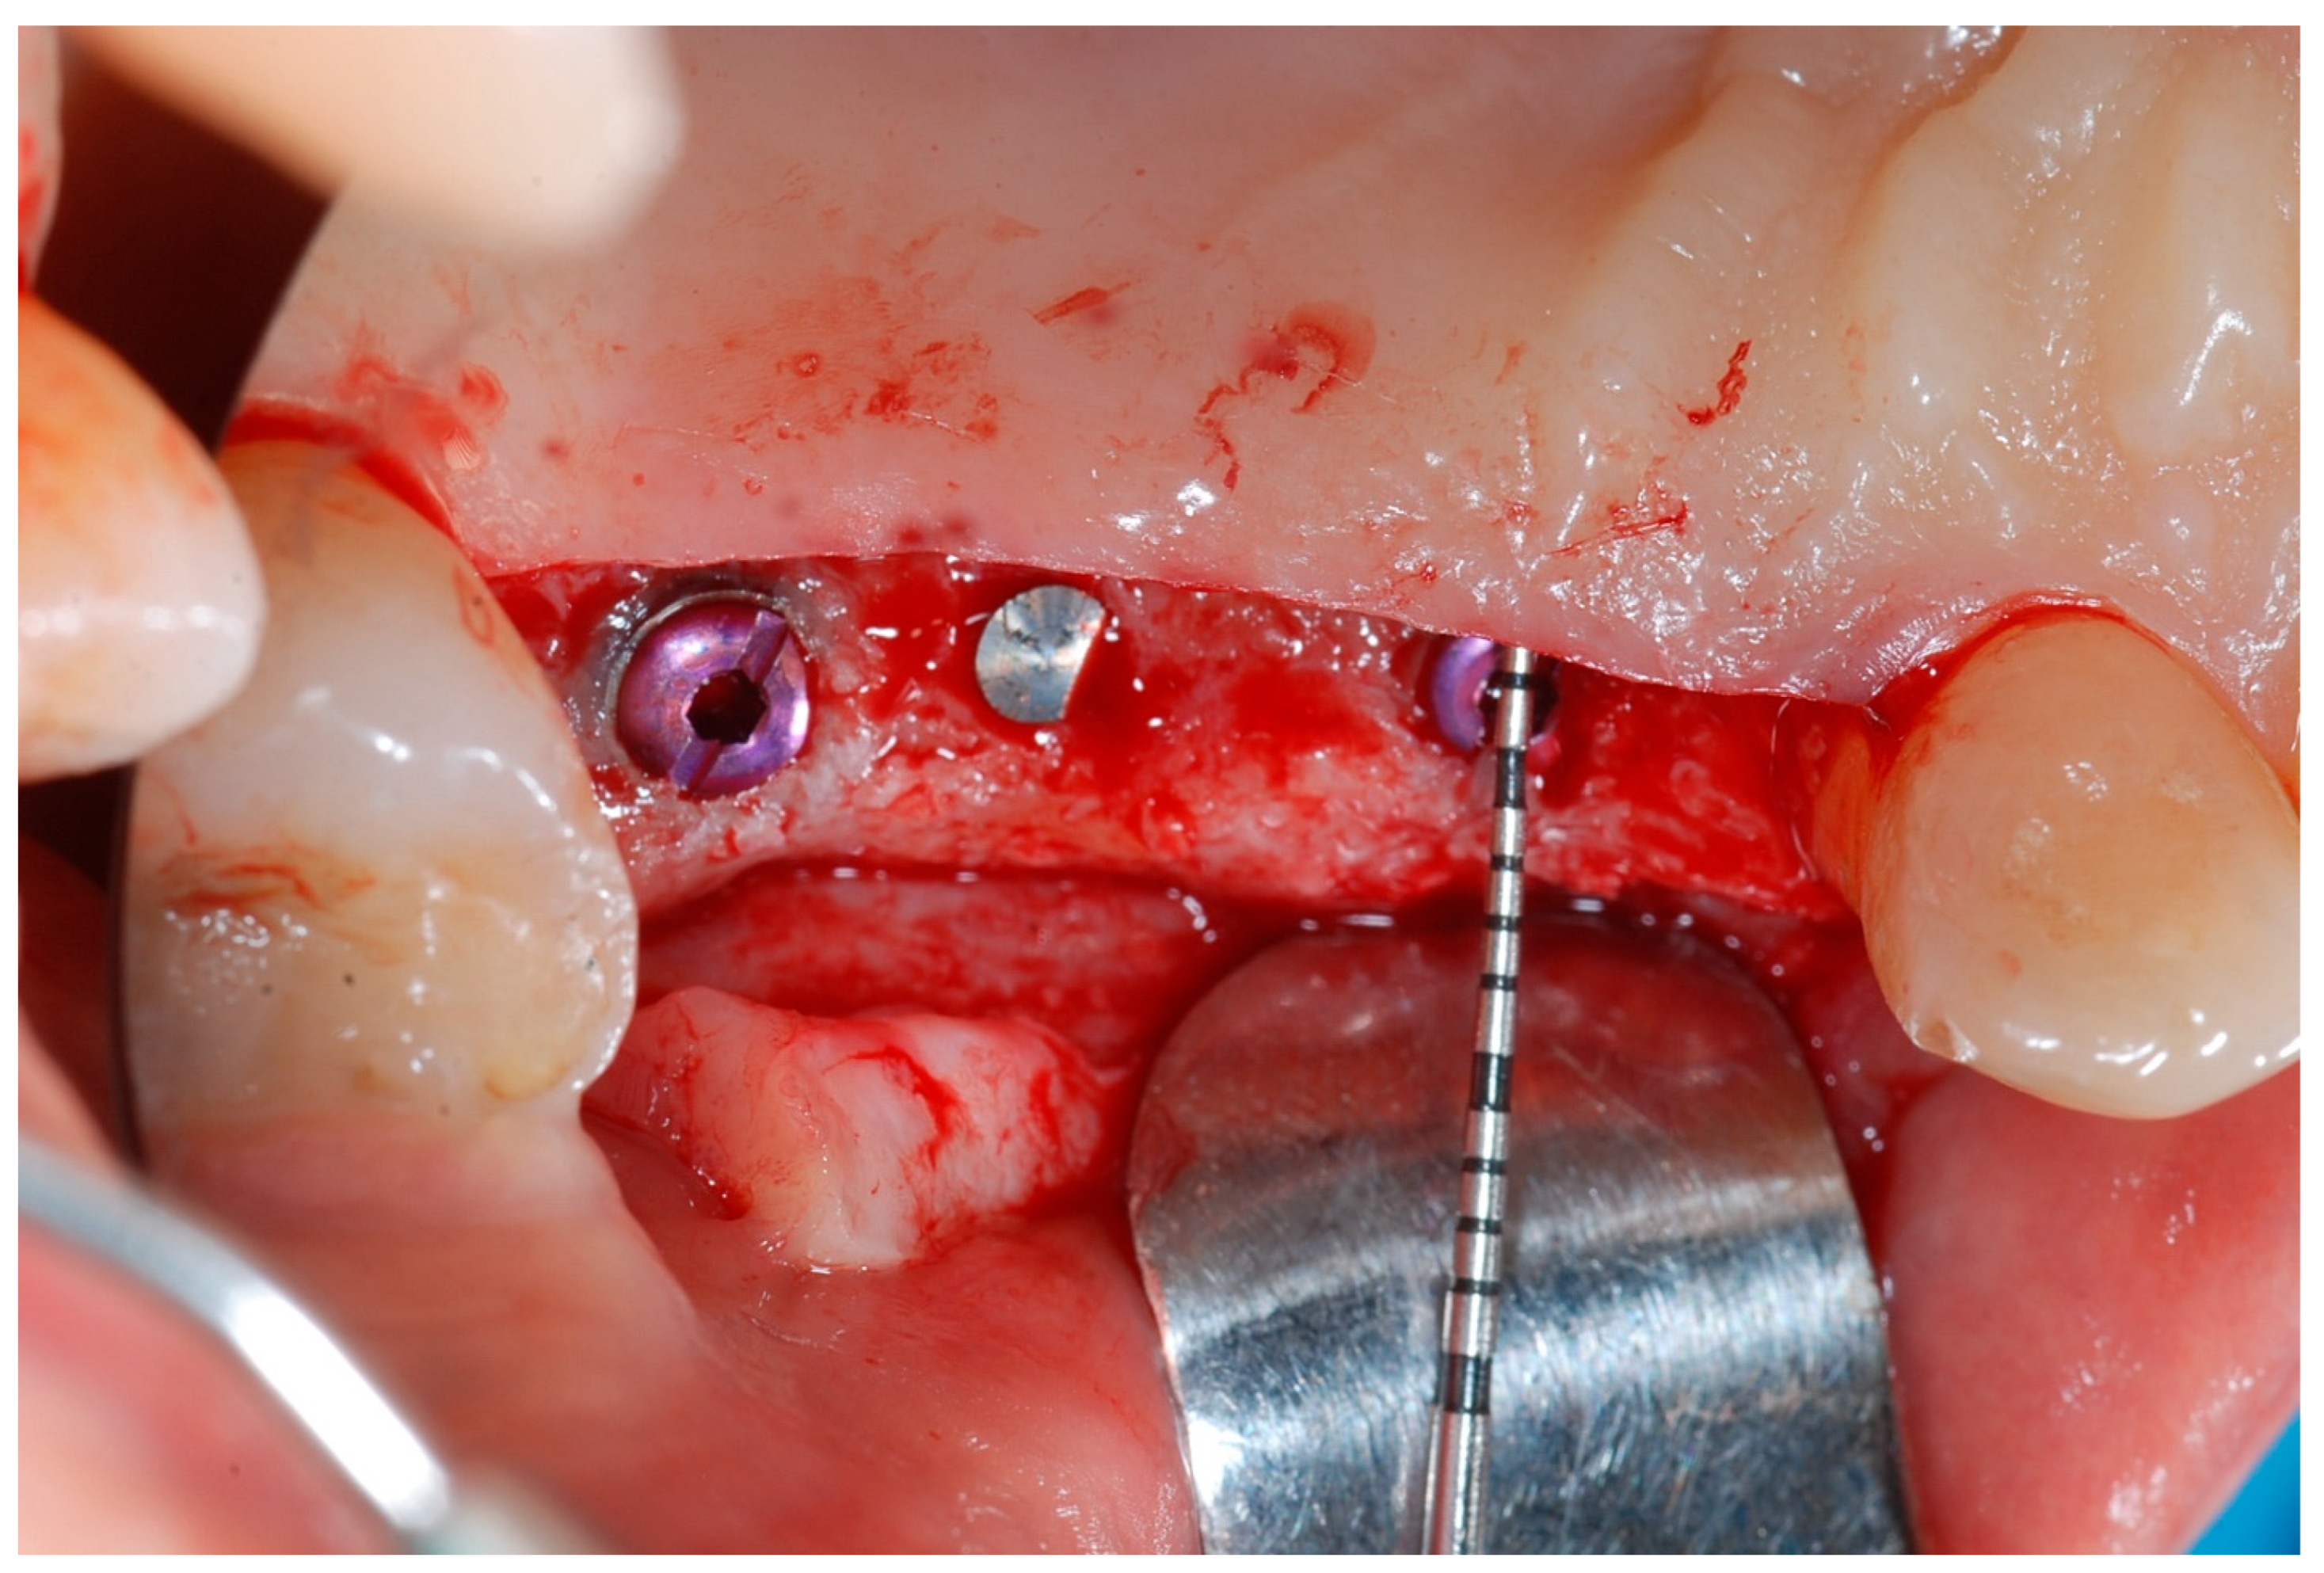

2.4. Re-Entry Surgery (T1)

Six months following augmentation, re-entry surgery was carried out to uncover the implants and connect the healing abutments. Following chlorhexidine rinses and the injection of local anesthetics, crestal incisions as well as releasing incisions along the same lines as the ones during augmentation surgery were performed. Mucoperiosteal flaps were raised in order to visualize the augmented bone volume (Figure 9 and Figure 10).

Figure 9. Reopening surgery showing no membrane residues and obtained buccal bone thickness.

Medicina 61 01814 g009

Figure 10. Reopening surgery showing no membrane residues and obtained buccal bone thickness.